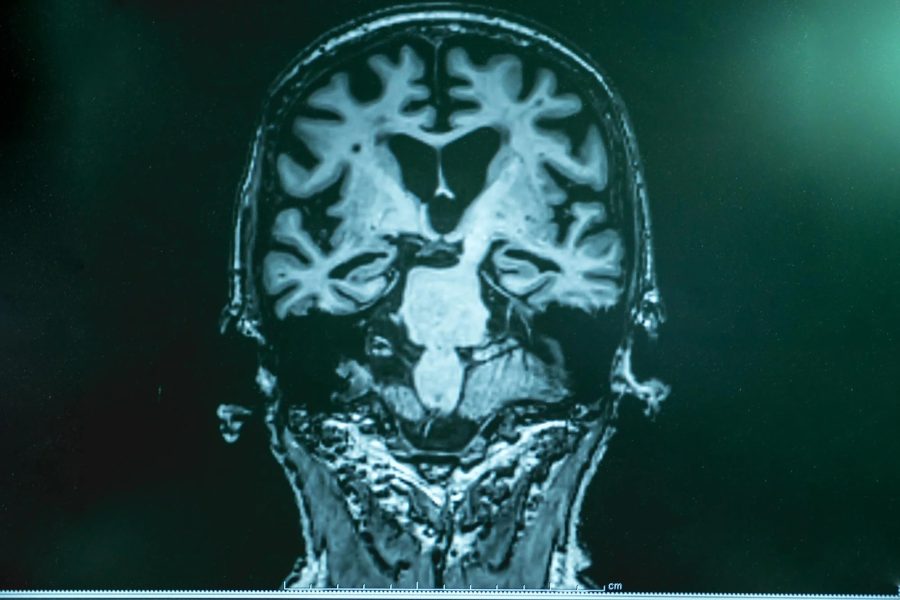

نوزادان و بیماران آلزایمر ویژگی مشابهی دارند!

نوزادان و افراد مبتلا به بیماری آلزایمر ویژگی بیولوژیکی غیرمعمولی را به اشتراک می‌گذارند: هر دو گروه سطح بالایی از یک نشانگر زیستی شناخته‌شده مرتبط با آلزایمر را نشان می‌دهند.

نوزادان و افراد مبتلا به بیماری آلزایمر چه شباهتی دارند؟ طبق یک مطالعه اخیر که تحت سرپرستی فرناندو گونزالس-ارتیز به عنوان نویسنده اول و پروفسور کای بلنوو به عنوان نویسنده ارشد در دانشگاه گوتنبرگ انجام شده است، هر دو گروه سطح بالایی از یک پروتئین خاص در خون خود نشان می‌دهند: تاو فسفریله، به‌ویژه نوع p-tau217 آن.

این پروتئین به‌طور گسترده‌ای به عنوان نشانگر زیستی بیماری آلزایمر شناخته شده است، جایی که افزایش حضور آن در خون به دلیل تجمع پروتئین بتا-آمیلوئید در پلاک‌های آمیلوئید در نظر گرفته می‌شود. با این حال، از آنجا که نوزادان این تغییرات پاتولوژیک را نشان نمی‌دهند، سطوح بالای p-tau217 که در نوزادان مشاهده می‌شود، احتمالاً ناشی از یک فرآیند توسعه‌ای کاملاً متفاوت و سالم است.

در یک مطالعه بین‌المللی بزرگ که با مشارکت محققانی از سوئد، اسپانیا و استرالیا انجام شد، نمونه‌های خونی بیش از 400 نفر مورد تجزیه و تحلیل قرار گرفت. این افراد شامل نوزادان سالم، نوزادان نارس، جوانان، بزرگسالان مسن و افرادی بودند که به بیماری آلزایمر مبتلا شده بودند. نتایج نشان داد که نوزادان بالاترین غلظت‌های p-tau217 را داشتند؛ سطوحی که حتی از بیماران آلزایمری نیز بالاتر بود. بالاترین سطوح در نوزادان نارس مشاهده شد و این سطوح به تدریج در طول ماه‌های اول زندگی کاهش یافت و در نهایت به سطوح معمول بزرگسالان رسید.